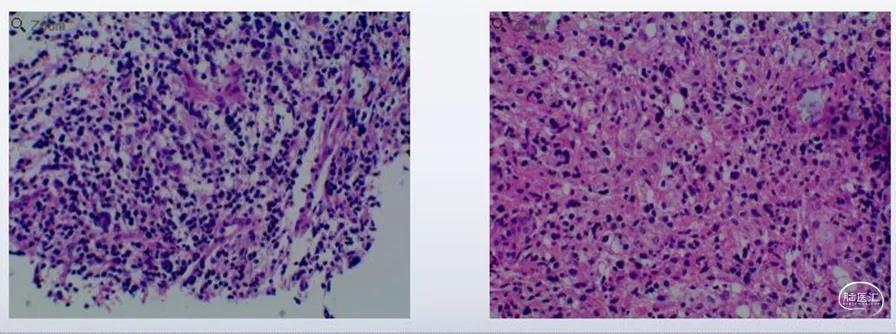

行立体定向活检术,术后病检示:高级别神经上皮来源肿瘤。免疫组化检测肿瘤细胞呈:ATRX(-),GFAP(灶+),IDH1R132H(-),Ki-67(Li:60%),Olig-2(+),P53(突变型),Bcl-6(-),CD10(-),CD20(-),CD21(-),CD23(-),CD3(-),CD30(-),CD5(-),C-myc(-),MUM1(-),Bcl-2(弱+),EBER(原位杂交)(-),CyclinD1(灶+),PAX5(-),CD43(-),ALK-1(弱+),H3K27M(-),SYN(-),S-100(局部+),NeuN(-),INI-1(+),LCA(-),TDT(-),MPO(-),CD34(-),Nestin(+),H3.3 G34R(-)。

最终整合诊断:结合镜下形态、免疫表型及分子检测结果,考虑高级别胶质瘤,胶质母细胞瘤(WHO Ⅳ级)。